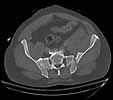

Post trauma day ten patient's xray shows failure of posterior construct. Plan was to perform revision orif once soft tissues resolve considerably for full anrterior fixation and posterior fixation. However, while Im away for holiday (on Post trauma day 15), pt is developing septic clinical appearance, and trauma suspects pelvic abcess near symphysis and performs I and D - finds nothing but no primary closure performed. Posterior tissues/incision continue to look healthy. Now is post trauma day 17, pt is still tubed/on dopamine/and wbc still elevated, anterior incision still packed open.

It appears from post-failure CT scan that the path of the more cephalad IS screw may be helpful to place a longer screw to engage opposite illiac wing as an option, or just anterior SI plates. not likely to do this tomorrow as he remains in a fragile clinical situation regarding his pulmonary status, and profound edema/induration around his pelvis/abdomen and thighs.